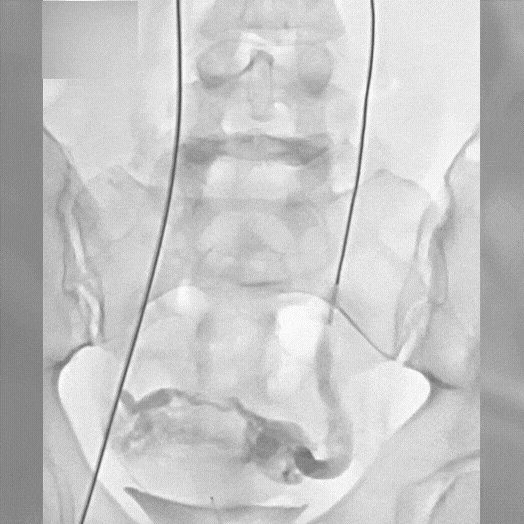

Ruby® XL Dr. Brandon Perry AdventHealth Orlando, FL

Zoomed in view of Ruby XL Detail

Coils Used: 8mm x 70cm POD XL and 70cm Packing Coil XL (bottom), 70cm Packing Coil XL (middle), 10mm x 35cm Ruby Standard and 12mm x 30cm Concerto (top)

Catheter: 80cm 5.5F Fogerty balloon w/ Cook 6 x 45cm Ansel-2 sheath